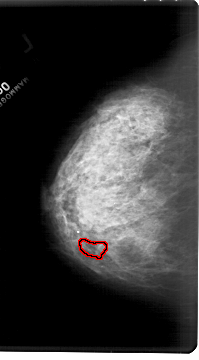

A_1469_1.LEFT_CC

LEFT_CC LINES 6826 PIXELS_PER_LINE 3781 BITS_PER_PIXEL 12 RESOLUTION 43.5 OVERLAY

FILE: A_1469_1.LEFT_CC.OVERLAY

TOTAL_ABNORMALITIES 1

ABNORMALITY 1

LESION_TYPE CALCIFICATION TYPE PLEOMORPHIC DISTRIBUTION LINEAR

ASSESSMENT 4

SUBTLETY 1

PATHOLOGY MALIGNANT

TOTAL_OUTLINES 1

BOUNDARY